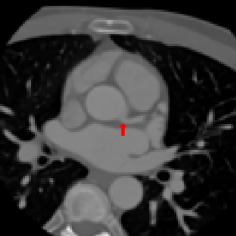

Refer to caption

(a) Original Resolution

(b) Voxel size: 1 mm

(c) Voxel size: 1.5 mm

(d) Voxel size: 3 mm

Figure 1: Axial slices from a CCTA scan, showing the right coronary ostium. The slices are shown at the original image resolution (left), resized to 1 mm (middle left), 1.5 mm (middle right) or 3 mm (right) isotropic voxels. The reference landmark location in the slices is indicated with a red arrow.